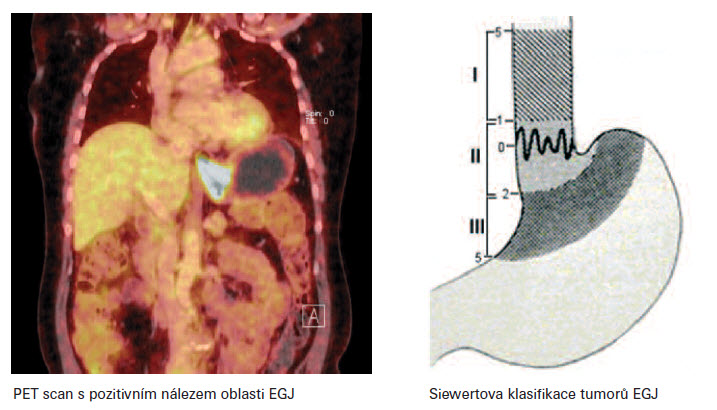

Strategie léčby adenokarcinomu oblasti EGJ je dána stadiem onemocnění. Toto je určeno nadále exaktním stanovením TNM parametrů. Diagnostika parametru T se opírá o CT,GF a též o endosonografický nález. Diagnostika N stadia, využívá dále i PET a FNB. Možná je i laparoskopická diagnostika, výjimečně VATS (videotorakoskopie). K chirurgické léčbě je určeno primárně stadium I. a II. U stadia II. je indikovaná pooperační adjuvantní chemoterapie u high risk T2N0 - v případě G3, lymfovaskulární invaze, neurovaskulární invaze a mladého věku pacientů. Dále v případě T3N0, T1-2 N1. Možná je i perioperační chemoterapie ECF (3 cykly před operací, 3 cykly po operaci). Stadium III. je indikované k chirurgické léčbě v případě dobré odpovědi na neoadjuantní onkoterapii. Neoadjuvantní léčba zvyšuje počet radikálních operací. Onkologická léčba po chirurgickém resekčním výkonu je dále též korigovaná typem resekce - R0, R1 a definitivním pTpNpM. Typ resekčního výkonu můžeme stanovit pomocí Siewertova doporučení, klasifikace adenokarcinomu oblasti EGJ.

Siewertova klasifikace adenokarcinomu lokalizovaného v oblasti kardie (Siewet et. al 1987 Mnichov) dělí tumory do tří typů. Typ I. - centrum tumoru leží 1-5cm orálně od EGJ. Typ II. - centrum tumoru infiltruje EGJ, tumor je lokalizovaný od 1 cm orálně až 2 cm aborálně od junkce. Typ III. - centrum tumoru je lokalizovano 2-5 cm pod EGJ. Dle Siewertovy klasifikace, je pak stanoven typ chirurgického resekčního výkonu. Pro typ I. se jedná o subtotální esofagektomii s proximální resekcí žaludku s lymfadenektomií paraezofageální a horního břišní kompartmentu. K obnovení kontinuity zažívacího traktu je možno využít gastropastiku zbylé části žaludku (velká křivina, antrum) či interpozitum kličkou jejuna dle Rouxe či koloplastiku. Pro typ II. a III. je indikována totální gastrektomie s distální resekcí jícnu a lymfadenektomií dolního mediastina s D2 břišní lymfadenektomií. Obnovení zažívacího traktu je konstruováno zpravidla jejunoplastikou. Součástí chirurgických resekčních výkonů je i omentektomie. V literatuře je možno se setkat i s „maximálním" resekčním výkonem typu totální gastrektomie se subtotální ezofagektomií s koloplastikou. Výkon je ale zpravidla zatížen vysokou morbididou doprovázenou i vyšší mortalitou. Invaze tumoru do bránice, jater - T4 v případě N0-1, za předpokladu případné resekability R0, není po neoadjuvantní léčbě s dobou odpovědí kontraindikací k chirurgické léčbě. V případě totální gastrektomie provádíme lymfadenektomii typu D2, lymfadenektomii D1 nepovažujeme za dostatečnou. Evropskými autory popisovaná vyšší morbidita i mortalita spojena s lymfadenektomií typu D2 je dána předně technickou peroperační komplikací, při které dochází ke krvácení a vynuceně ke splenektomii či resekci pankreatu, které nejsou běžnou součástí chirurgické léčby. Zásadní je lymfadenektomie v bezprostředním okolí tumoru, kompletní resekce malého omenta a lymfadnektomie oblasti a. gastrica sinistra a trunkus celiakus. S paraezofageální lymfadenektomií a lymfadenektomií oblasti bifurkace trachei nebývají zpravidla technické potíže. Spádové lymfatické uzliny žaludku dělíme dle modifikované klasifikace dle JRSGC (Japanese Research Society for Gastric Cancer) do tří kompartementů. Lymfatické uzliny stanice 1.-6. tvoří I., 7.-11. II. a 12.-16. III. kompartment. Dle některých autorů tvoří LU skupiny 15. a 16. kompartement IV. Lymfadenektomie typu D1 spočívá v odstranění uzlin a přilehlé tukové tkáně kompartmentu I., D 2 I. a II. Dle TNM klasifikace tvoří metastázy v LU III. kompartementu marker M1. Skupiny lymfatických uzlin dle stanic: 1. parakardiální při malé křivině, 2. parakardiální při velké křivině, 3. uzliny podél malého zakřivení žaludku, 4. podél velkého zakřivení, 5. podél suprapylorické, 6. infrapylorické, 7. uzliny podél a. gastrica sinistra, 8. podél a. hepatica communis, 9. v oblasti truncus coeliacus, 10. v oblasti hilu sleziny, 11. podél av. lienalis, 12. oblast ligamentum hepato-duodenale, 13. retropankreaticky v oblasti hlavy slinivky břišní, 14. podél av. mesenterica superior, 15. podél av. colica media, 16. podél abdominální aorty.